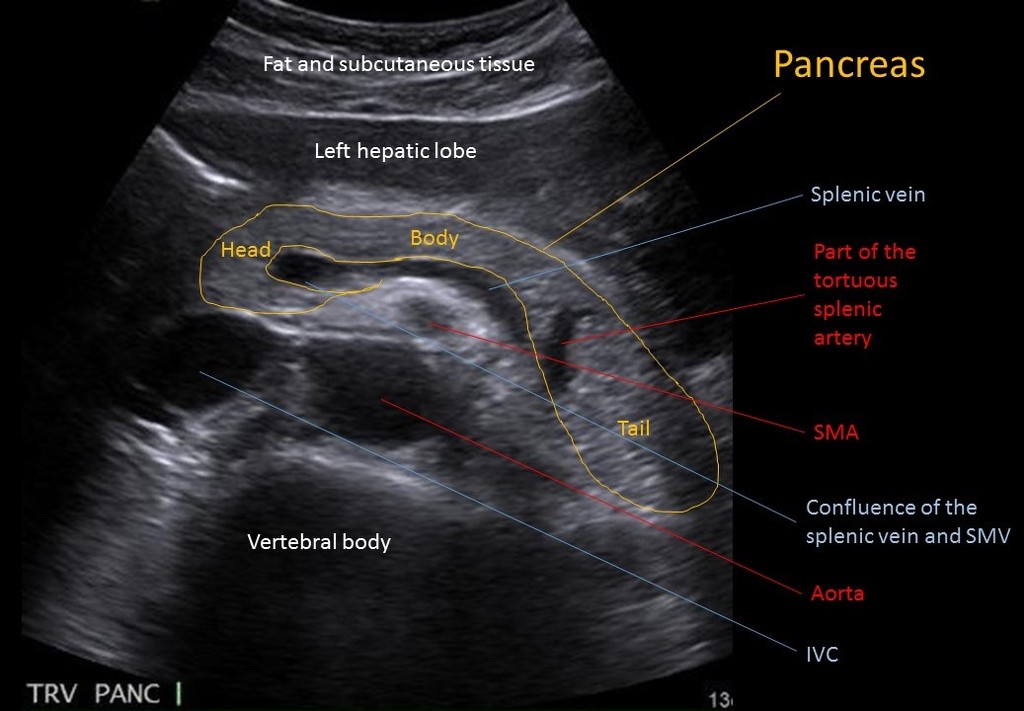

보통 상복부초음파영상에서 췌장을 촬영할 때는 위와 같은 영상을 머리에 떠올리고 촬영하게 됩니다. 새 부리모양의 췌장 두부, 비장정맥(splenic vein)의 앞쪽으로 췌장의 몸통이 위치하면서 췌장꼬리는 비장을 향해 뒤로 꺽이는 모양이 전형적인 양상입니다.

여기서 많은 분들이 착각하는 부분이 췌장꼬리와 비장정맥의 관계입니다. 위의 그림에서도 노란색 글자로 “Tail”이라 표시되어있는 부위를 췌장꼬리라 인식하는 경우가 대부분이고, 대부분의 교과서나 자료들에서도 같은 식으로 묘사하지만 실제로 해당부위가 췌장꼬리인 경우는 거의 없습니다.

이제 다시 위의 초음파 횡단면영상을 보시면, 아니나다를까 췌장 뒤쪽에서 확인할 수 있는 비장정맥이 췌장 몸통부분까지만 확인할 수 있으며, 꼬리(Tail이라고 표시된 부위)라고 표시하고 있는 부위에는 비장정맥이 위치해있지 않고 있습니다. 이 부위가 과연 췌장 꼬리부위가 맞다고 할 수 있으려면 반드시 확인해야 하는 것이 해당부위의 뒤쪽에 왼쪽 콩팥이 위하는지 여부입니다.